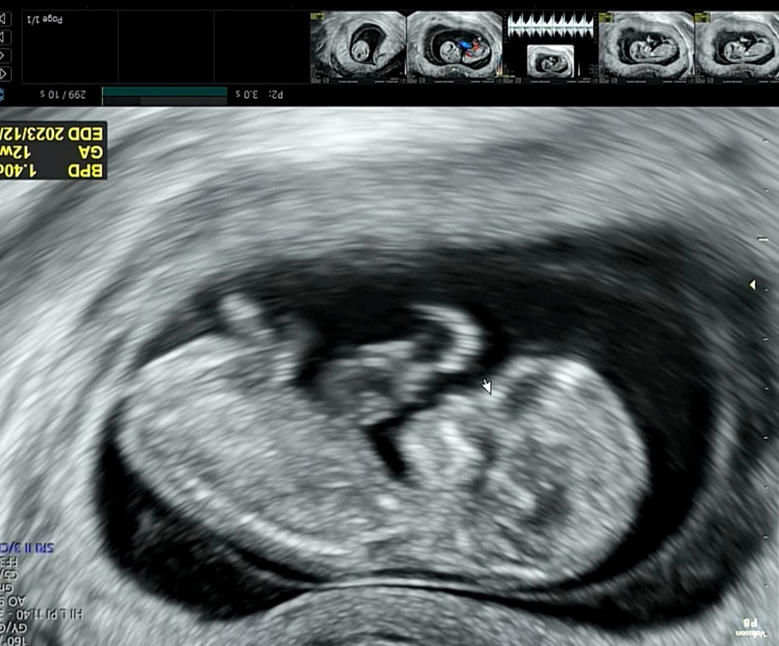

이제 우리 짱튼이가 13주가 되었는데요. 11주차에 난임병원을 졸업하면서 정밀초음파를 한번 보았습니다.

1차 기형아검사 시기는 11주부터 13주 사이에 진행합니다.

정밀초음파를 보면서 전반적인 태아의 성장발달을 관찰하는데요.

아기의 코뼈가 형성이 되었는지, 머리와 장기들이 형성되고 있는 중인지도 살펴봅니다.

코뼈 역시 길이를 재기도 하고요.

검진내용 (정밀초음파)

목투명대가 1mm - 3mm 사이이면 정상이라고 합니다.

3mm가 넘어가면 다운증후군이 의심된다고들 하는데요.